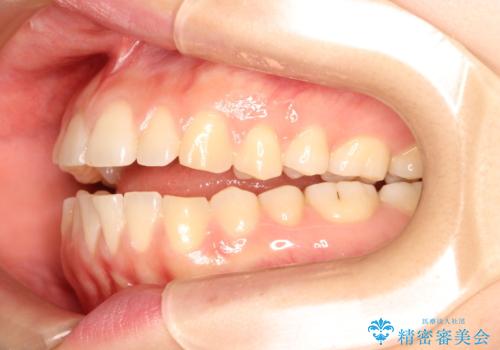

上下の前歯が当たらない インビザラインによる開咬の矯正治療

- 上下の前歯の間に隙間があるとのことで来院されました。

開咬とよばれる、奥歯しか上下の歯が接触していない状態でした。

インビザラインにて矯正治療を行うこととなりました。

使用時間を守っていただけたので、比較的スムーズに矯正を終了することができました。

前歯で物が咬み切れるようになり、喜んでいただけました。

舌の使い方が上手ではなかったので、治療と同時に舌のトレーニングを行いました。

舌の使い方も矯正治療と非常に関係があります。